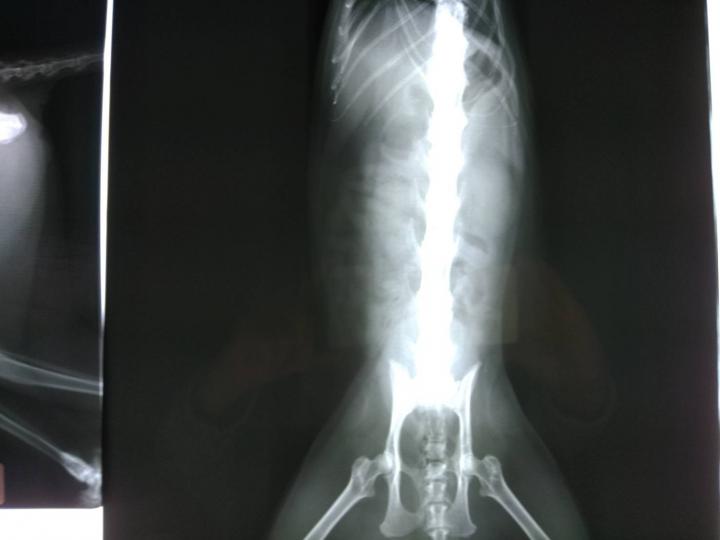

あれ?でも、お母さん。何で背骨のレントゲンばかりなの?骨軟骨異形成症候群だったら、足か尾だけだよね?

え?先生が「背骨にカルシウムが蓄積してる」って

あ、それは骨軟骨異形成じゃなくて、変形性脊髄症じゃないかな?

調べてみたらですね、変形性脊髄症は、何らかの原因で、体が背骨を補強しようとして、カルシウムが集まり、それが突起などの変形をして場合によっては痛みから歩行困難等になるらしいです。

直接、先生から聞いていないので解らないのですが、骨折の後もあったとか。